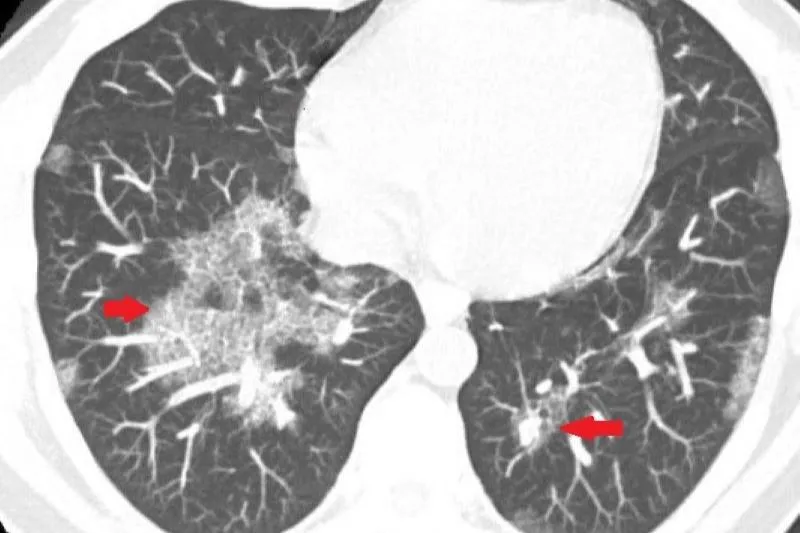

間質性肺病

肺炎

肺部白影

罕見疾病

肺活量

無法呼吸